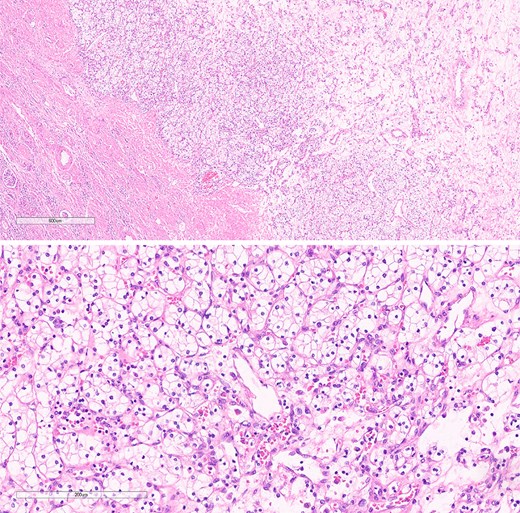

Histopathological specimens of the kidney revealed clear cell RCC (ccRCC) (Fig. 5), measuring 4.0 × 4.0 × 3.8 cm with a histologic grade of G2. The tumor growth was limited to the kidney, with all margins negative for invasive carcinoma. Tumor necrosis was present at 10%. Lymphovascular invasion was present. This case of RCC was staged as T1aN0M0 according to the TNM classification [8]. The sigmoid colon mass analysis revealed low-budding, well-differentiated adenocarcinoma, size 6.5 cm, with submucosal invasion (T1). There is no lymphovascular or perineural invasion. The margin was negative for both proximal and distal mesenteric margins. The remaining tissue examination revealed a tubular adenoma with focal high-grade dysplasia. There were negative results for metastatic carcinoma in all 12 lymph nodes from the specimen. In this case, the TNM staging for the sigmoid colon carcinoma was determined to be T1N0M0 [9].

The histological section of RCC shows clear cytoplasm and cellular morphology consistent with clear cell RCC.

The pathological analysis of the kidney mass was revealed to be ccRCC, measuring 6.0 × 4.7 × 3.5 cm with a histologic grade of G2. The tumor extension was limited to the lower pole of the right kidney. All margins were negative for invasive carcinoma, and 10% tumor necrosis was identified. In this case, the TNM staging of RCC was classified as T1bN0M0 [8]. The sigmoid colon mass was revealed to be grade G2—moderately differentiated, adenocarcinoma measuring 5 cm at the maximal diameter (Fig. 7). The cancer has shown invasion through the muscularis propria into the pericolic fatty tissue. Fortunately, the proximal resection, distal resection, and mesenteric resection margins showed no involvement by the invasive carcinoma. In addition, all of the 15 biopsied lymph nodes showed no metastasis. In this case, the sigmoid colon cancer was staged as T2N0M0 [9].